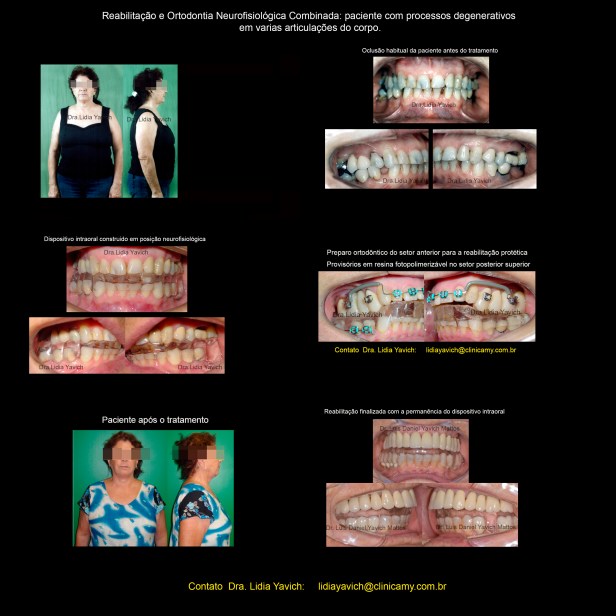

Nesta publicação relataremos um caso onde devolvemos à paciente uma boa qualidade de vida e pudemos oferecer uma reabilitação neuromuscular fisiológica combinada com uma ortodontia tridimensional, sempre mantendo a localização mandibular em equilíbrio com os planos musculares, com a articulação temporomandibular e com os planos dentários, conseguidos na primeira fase.

Neste caso, devido a vários processos degenerativos ativos em todo o corpo decidimos para proteger a paciente, manter a órtese.

Seus músculos foram desprogramados eletronicamente e foi construído um DIO dispositivo intraoral, ou órtese em posição neuromuscular fisiológica. Nas outras publicações se faz menção dos métodos cinesiográficos utilizados.

Modificações estéticas com o dispositivo em posição neuromuscular fisiológica em boca.

A paciente apresentava remissão da sintomatologia, o que nos permitiu trabalhar na recuperação da saúde, da estética e do sistema estomatognático da paciente.

A movimentação ortodôntica COM O DISPOSITIVO INTRA-ORAL FOI INICIADA. O primeiro objetivo foi a verticalização do molar inferior do lado direito e a recuperação do espaço do 46 que nos permitisse a instalação do implante.

O segundo objetivo na continuação da reabilitação neuromuscular fisiológica combinada com a ortodontia tridimensional foi a vestibularização do setor anterior superior possibilitando a reconstrução anatômica adequada dos dentes.

Neste caso o planejamento inicial foi manter um dispositivo intraoral após a reabilitação, já que a perda dimensional era muito grande.

Fotografias intraorais pre e pós tratamento.

Fotografias intraorais pre e pós tratamento.

Modificações estéticas e posturais da paciente pré-tratamento e após a reabilitação neuromuscular fisiológica.